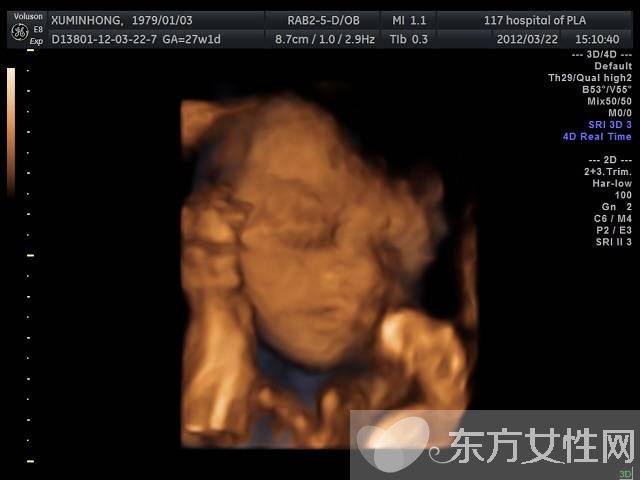

普通B超和彩色B超都是二維平面圖像,這兩種技術(shù)仍在使用,但由于觀測效果較為依賴羊水量和胎兒體位,一旦在懷孕晚期羊水減少或者胎兒面向母親的背部,觀測效果就不太理想。而且,二維圖像不能滿足準(zhǔn)媽媽們“看到”寶寶模樣的愿望。因此,最近幾年,隨著計算機技術(shù)的發(fā)展,又出現(xiàn)了三維B超,也就是將二維圖像合成模型,透過屏幕可從各個方位觀察胎寶寶。

三維彩超、四維彩超的圖像是后期生成的,并不是說觀察到的圖像就是三維、四維的,而是仍然用普通彩超觀察,然后通過儀器中的轉(zhuǎn)換軟件將觀察到的平面圖像轉(zhuǎn)成三維、四維的立體圖像,使不懂B超圖像的人也能看出胎兒的模樣。而三維和四維的區(qū)別就在于在一個“時間維”,也就是說,前者是圖片,后者是錄像,可以讓孕媽媽看到胎兒一連串的動作。